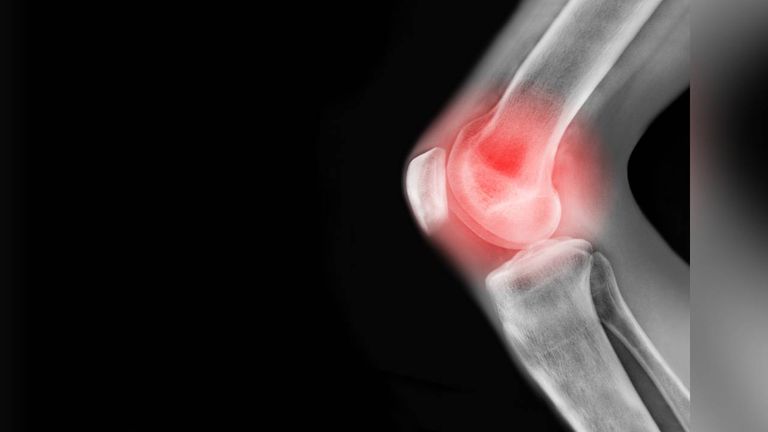

Ciudad de México.- El desgaste de cartílago es una condición que se genera a partir de una lesión repentina, como una lesión deportiva, o un desgaste gradual ocurrido por osteoartritis o artrosis de rodilla, e incluso por el desgaste que genera el paso de los años, causando Inflamación, dolor, rigidez y limitación del movimiento.

El testimonio de la paciente da cuenta de cómo con unos meses de aplicarse la terapia a base de inductores sus rodillas han mejorado y eso lo demuestra la radiografía que presenta para que otros pacientes con este padecimiento conozcan estos resultados, que le han permitido dejar el bastón.

Al mostrar los estudios de la paciente mencionó cómo en comparación con una radiografía anterior se puede ver que se incrementó el cartílago, «sin contar que la cistatina ya está elevada, ya están filtrando más los riñones y va bastante bien”, señaló el médico al darle la honra y gloria a Dios por estos resultados.